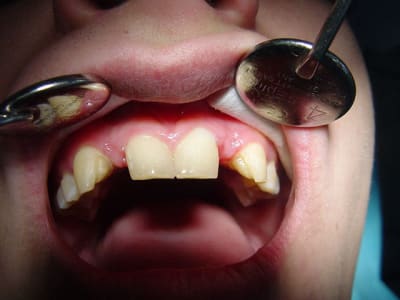

bonjour, le cas :

Dsc00091 vo4p11 - Eugenol

rebonjour, le provisoire : excuse pour la qualité des photos

(sony cybertshot première génération 2.1mp....)

préparations pour bridge collé ...des commentaires?